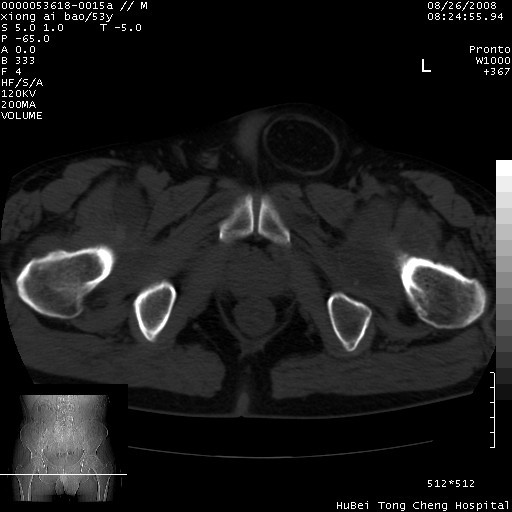

标题: CT15583:M,53Y。请老师指教分析骨盆及其他病变。 [打印本页]

标题: CT15583:M,53Y。请老师指教分析骨盆及其他病变。

股骨头坏死/腹股沟疝。

双侧股骨头无菌坏死,左侧腹股沟斜疝。

非常典型病例,双侧股骨头坏死伴双髋关节周围软组织肿胀,左腹股沟疝。

双侧股骨头坏死伴双髋关节周围软组织肿胀,左腹股沟疝。

双侧骨股头无菌性坏死,左侧腹股沟疝

双侧髋关节肿胀明显,感觉还不能排除结核。

考虑双侧髋关节结核,左侧腹股沟疝